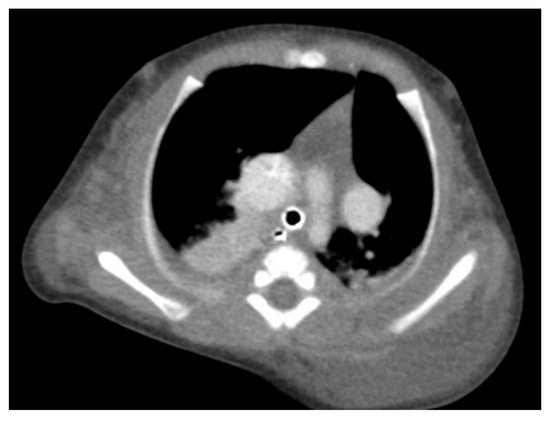

Through thoracic CT, we found SVC with a diameter of 15 mm (Figure 1), a venous collector with a 12 mm in diameter connected to the SVC and identified at the level of a plane passing through the middle of the left superior pulmonary lobe (Figure 2). The venous structure continues superiorly with the left brachiocephalic venous trunk, which was dilated up to 12 mm (Figure 3) and inferiorly with a left pulmonary vein. The pulmonary trunk appeared shorter, with a diameter of 6 mm, right pulmonary artery = 5.4 mm and left pulmonary artery = 5.6 mm (Figure 4 and Figure 5). We have identified traits of pulmonary consolidation (Figure 6).

Figure 1.

Dilated SVC.